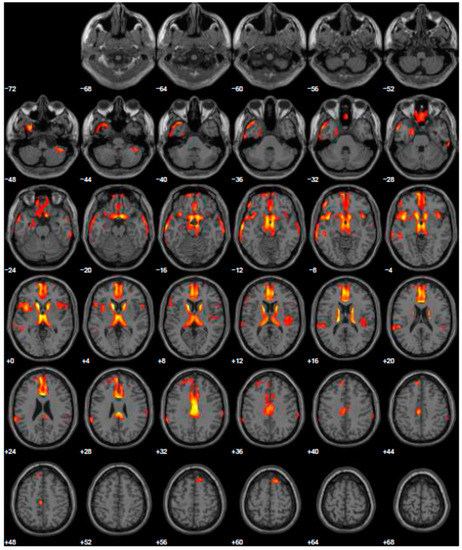

Given psychiatric symptoms reported, we changed the current treatment starting L-dopa and prescribed the FDG-PET, because of the severe anxiety induced in family members of this young PD patient. FDG-PET showed extended hypometabolism in the right and left inferior frontal gyrus and in part of the prefrontal lateral areas (Figure 2). A further cognitive assessment by MMSE remained normal and even the second level of neuropsychological evaluation resulted normal. After the prescription of L-dopa at the dosage of 300 mg daily, motor symptoms disappeared and patient’s wife reported a profound improvement of behavior, with disappearance of ICDs.

Figure 2.

Brain PET with 18F-FDG. Images highlight brain regions consistently found the analysis (Statistical Parametric Mapping software SPM 5 (p = 0.05). Diffuse hypometabolism in the left middle temporal gyrus, right and left inferior frontal gyrus, left middle frontal gyrus, left posterior cingulate, left inferior parietal lobule, right lentiform nucleus (putamen), right caudate head, left thalamus, left parahippocampal gyrus, right red nucleus (midbrain), left cerebellum pyramis, right and left cerebellum inferior semi-lunar lobule, right and left cerebellum posterior lobe tuber, right cerebellum anterior lobe nodule, left cerebellar tonsil.